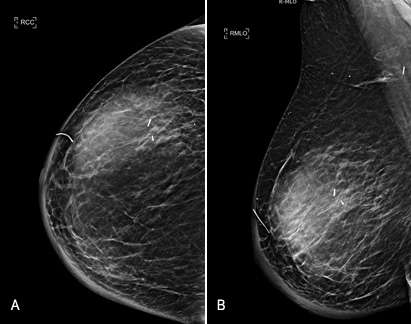

On mammogram, seromas often appear as well-defined masses that are found within or adjacent to a surgical site. When the breast is compressed during a mammogram, the fluid collection may slightly change in shape or size. This compression effect observed on mammograms may aid in distinguishing these fluid-filled structures from solid masses.